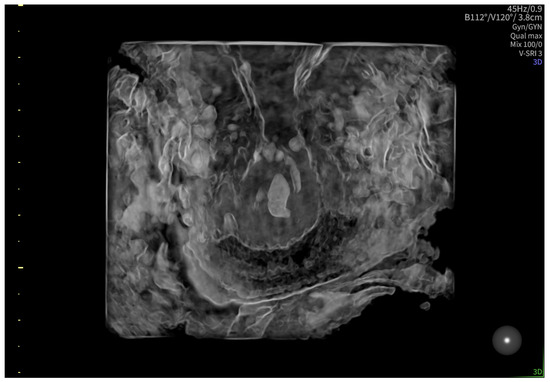

2. Case Presentation